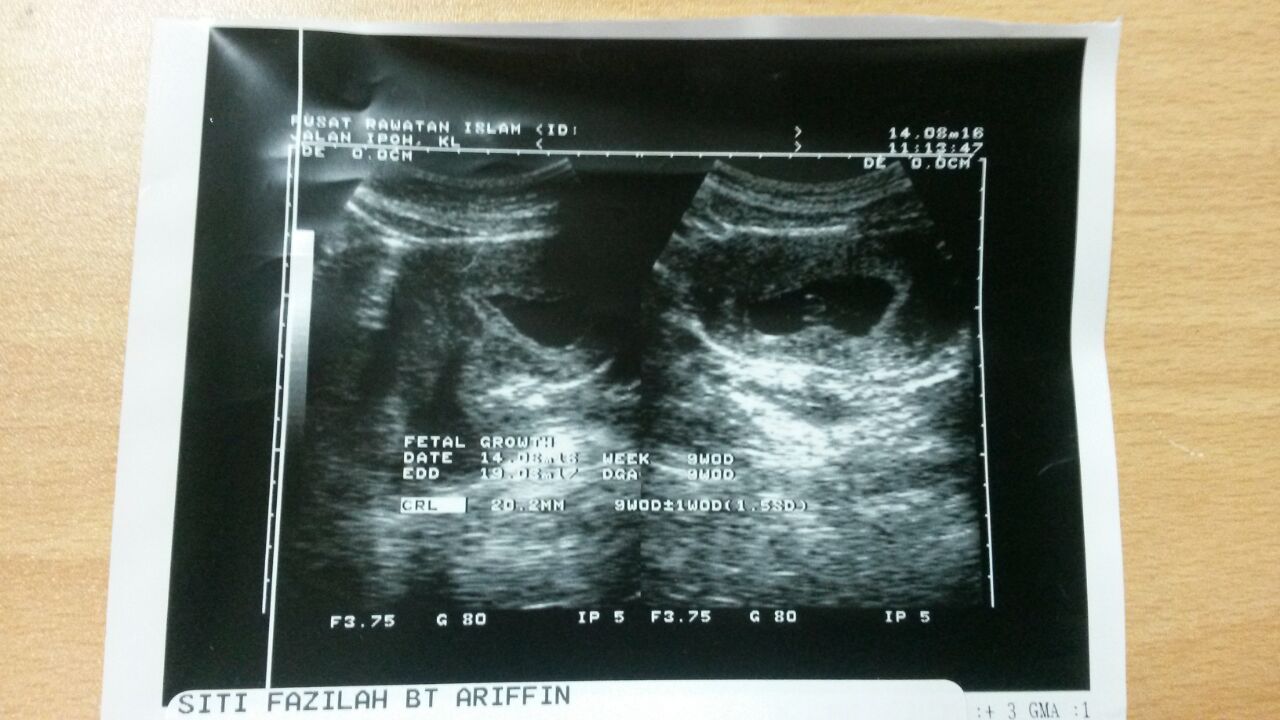

Perut dah membesar. Minggu lepas check up baby semua ok. Jantung, kedudukan baby semua ok. 2nd pregnant ni lain sikit dari yg 1st pregnant.